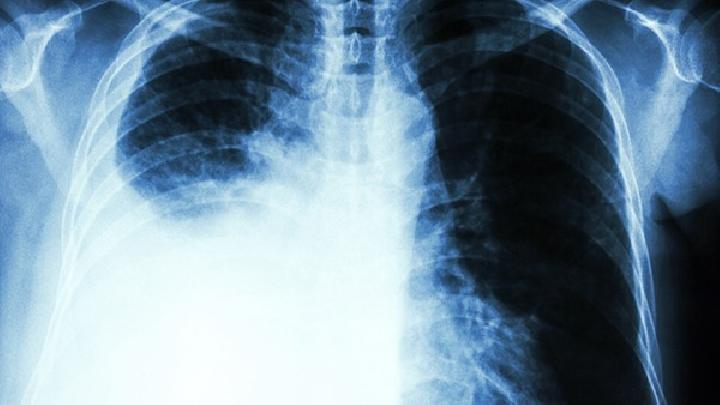

肺纤维化

肺间质纤维化治疗相对来说棘手,现代医学治疗主要是激素,但是根据肺纤维化分型的不同而对激素的...